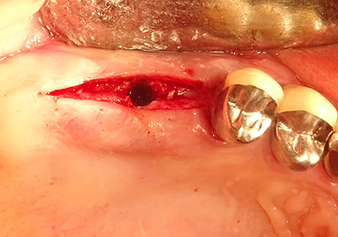

Following atraumatic preparation of the mucoperiosteal flap, the implant position was marked with the I1 instrument and the site prepared – until initial resistance was felt. Piezosurgical instruments were used in an up and down movement without any pressure being exerted. The piezoelectric vibration produced the desired and efficient cavitation.

The I2A instrument (diameter 2.0 mm) was then used to perforate the sinus floor intermittently and on the smallest scale possible. This special piezosurgical method ensures that the Schneiderian membrane is not damaged. When the Z25P was used, the membrane was already lifted slightly by the coolant supplied via the instrument tip (Fig. 3). The coolant quantity was just 50% in order to avoid high pressure in the implant bed.